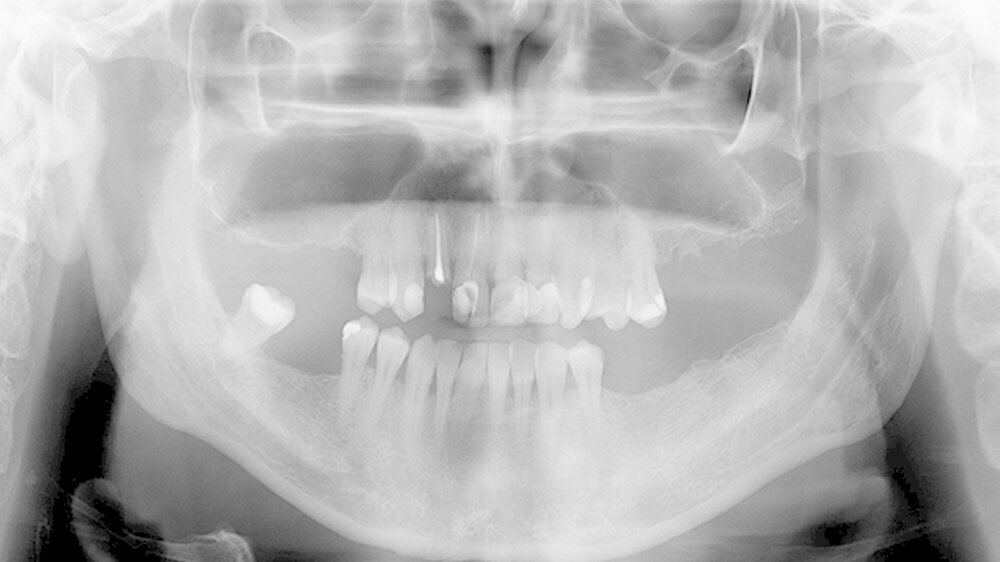

Oralchirurg Marcus Stoetzer arbeitete drei Monate lang im Feldlager der Bundeswehr in Mazar e Sharif - insgesamt behandelte er in Afghanistan 298 Soldaten. Die Bilder zeigen, aus welchem Grund sie zu ihm kamen.